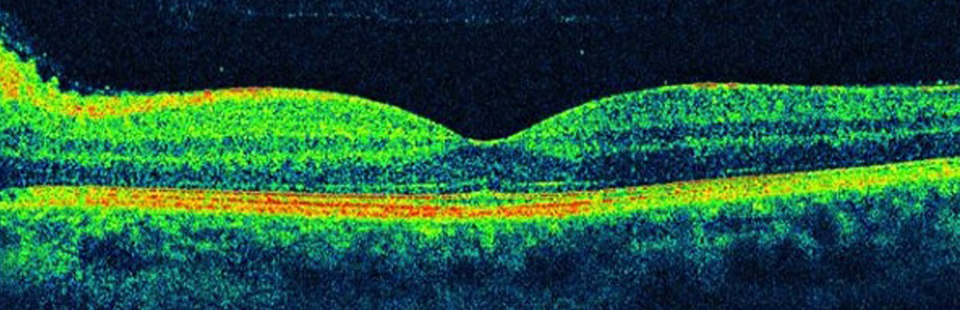

Диагностика зрения: Когерентная томография сетчатки

Раздел: Фотоальбом решений